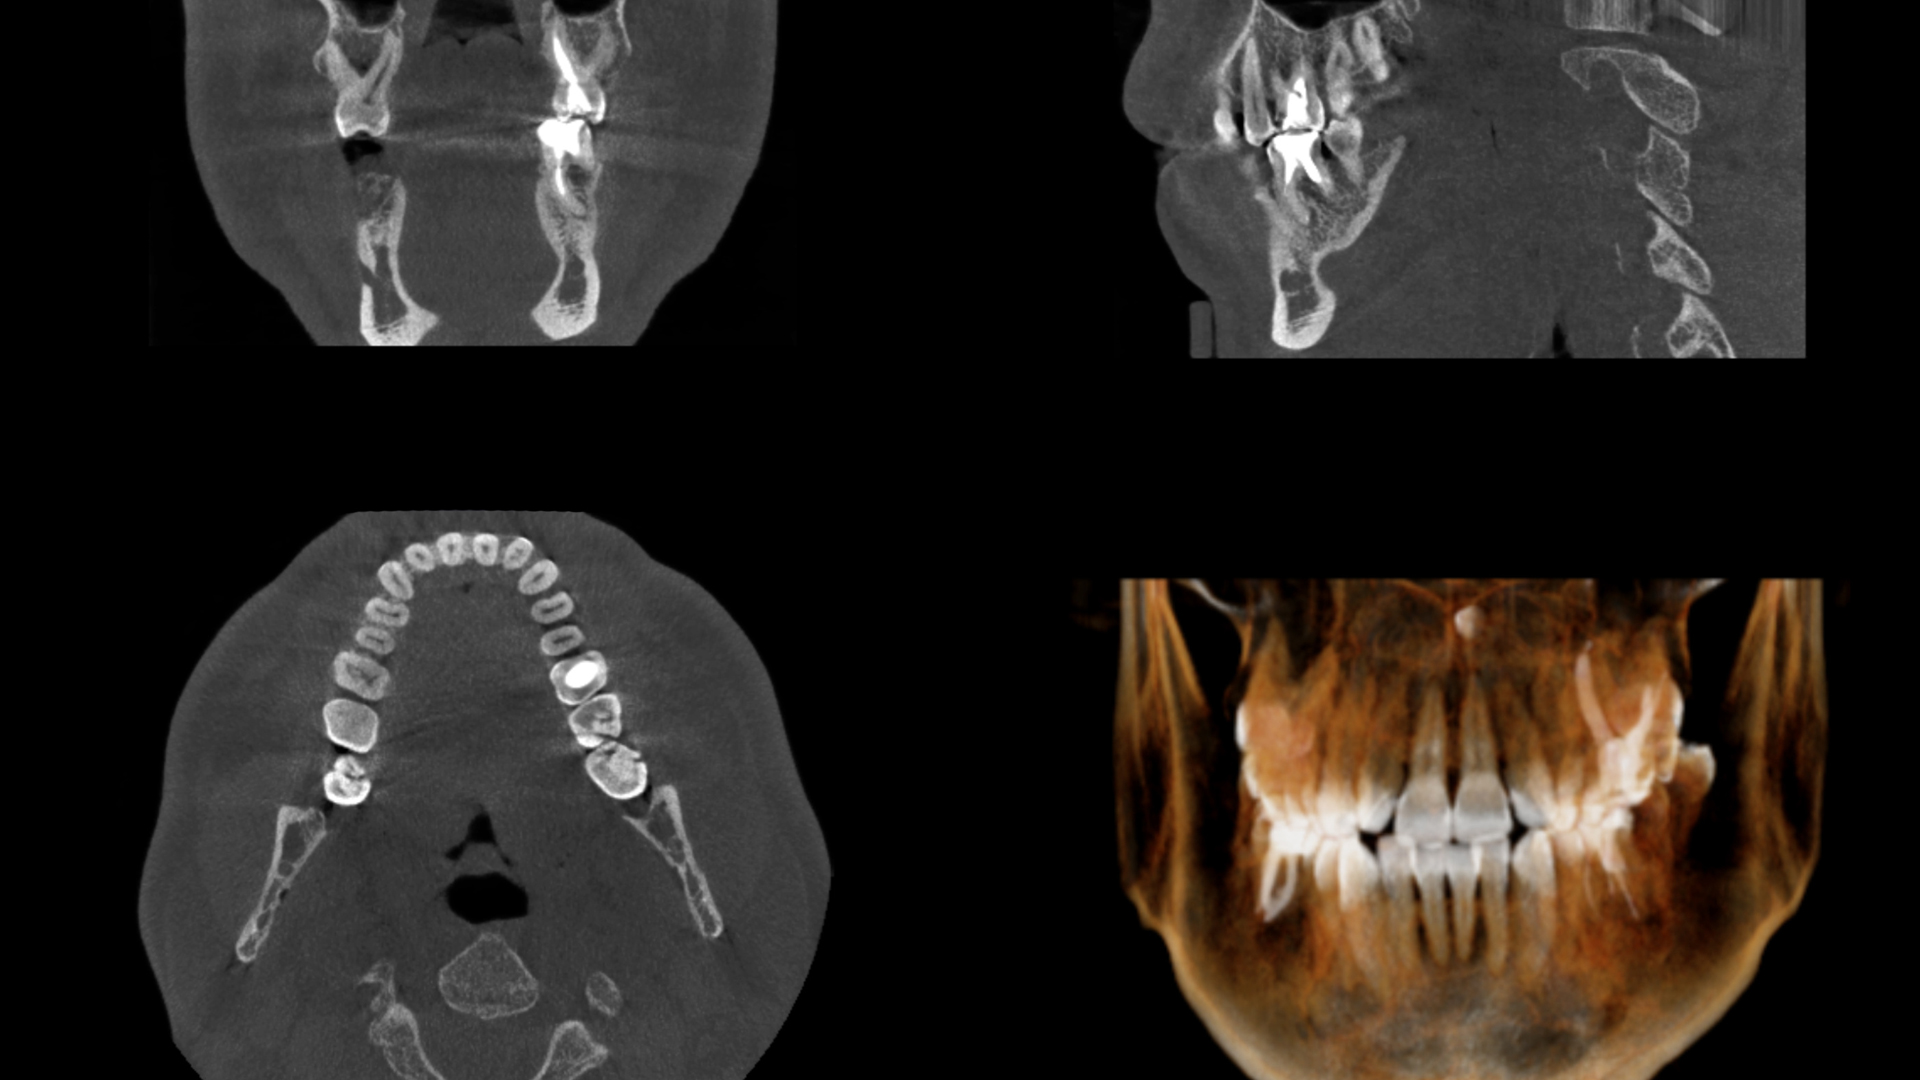

A cone beam CT scan involves a special type of x-ray that allows us to see the details of your oral and facial health. This scan is more than just a typical x-ray, since it allows us to identify nerve pathways, soft tissue and bone before providing you with treatment. This gives us a clear view of your oral health so that treatment is easier and more effective for you. The scan takes just seconds in our office and provides us with a highly detailed image.

Most often, you'll need a CT scan before you have oral surgery performed in our office. This is because the CT scan allows us to identify soft tissues, bone and even nerves that could come into play when performing a surgical procedure. You might even need to have this scan done if you come to us with an emergency or when we are trying to find a problem that you're experiencing. The amount of radiation used to produce an image using the CT scan machine is minimal and considered safe and beneficial for most patients.